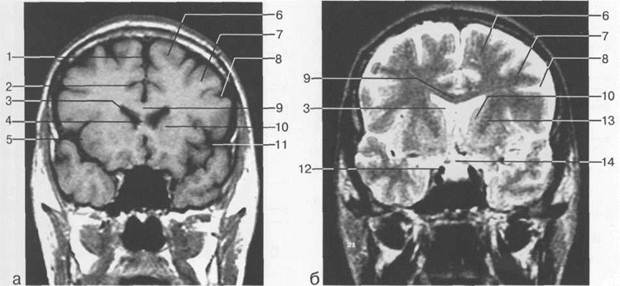

Рис. 1.16. Уровень задних отделов тел боковых желудочков. Коронарные МРТ-срезы: а — Tl-взвешенное

изображение; б — Т2-взвешенное изображение.

1 — верхняя теменная долька; 2 — поясная борозда; 3 — цистерна большой вены мозга (вены Галена); 4 — четвертый желудочек; 5 — предцентральная извилина; 6 — центральная борозда; 7 — постцентральная извилина; 8 — надкраевая извилина; 9 — поясная извилина; 10 — латеральная щель; 11 — верхняя височ­ная извилина; 12 — нижняя височная извилина; 13 — намет мозжечка; 14 — зубчатое ядро; 15 — спинной мозг; 16 — треугольник бокового желудочка; 17 — миндалина мозжечка.